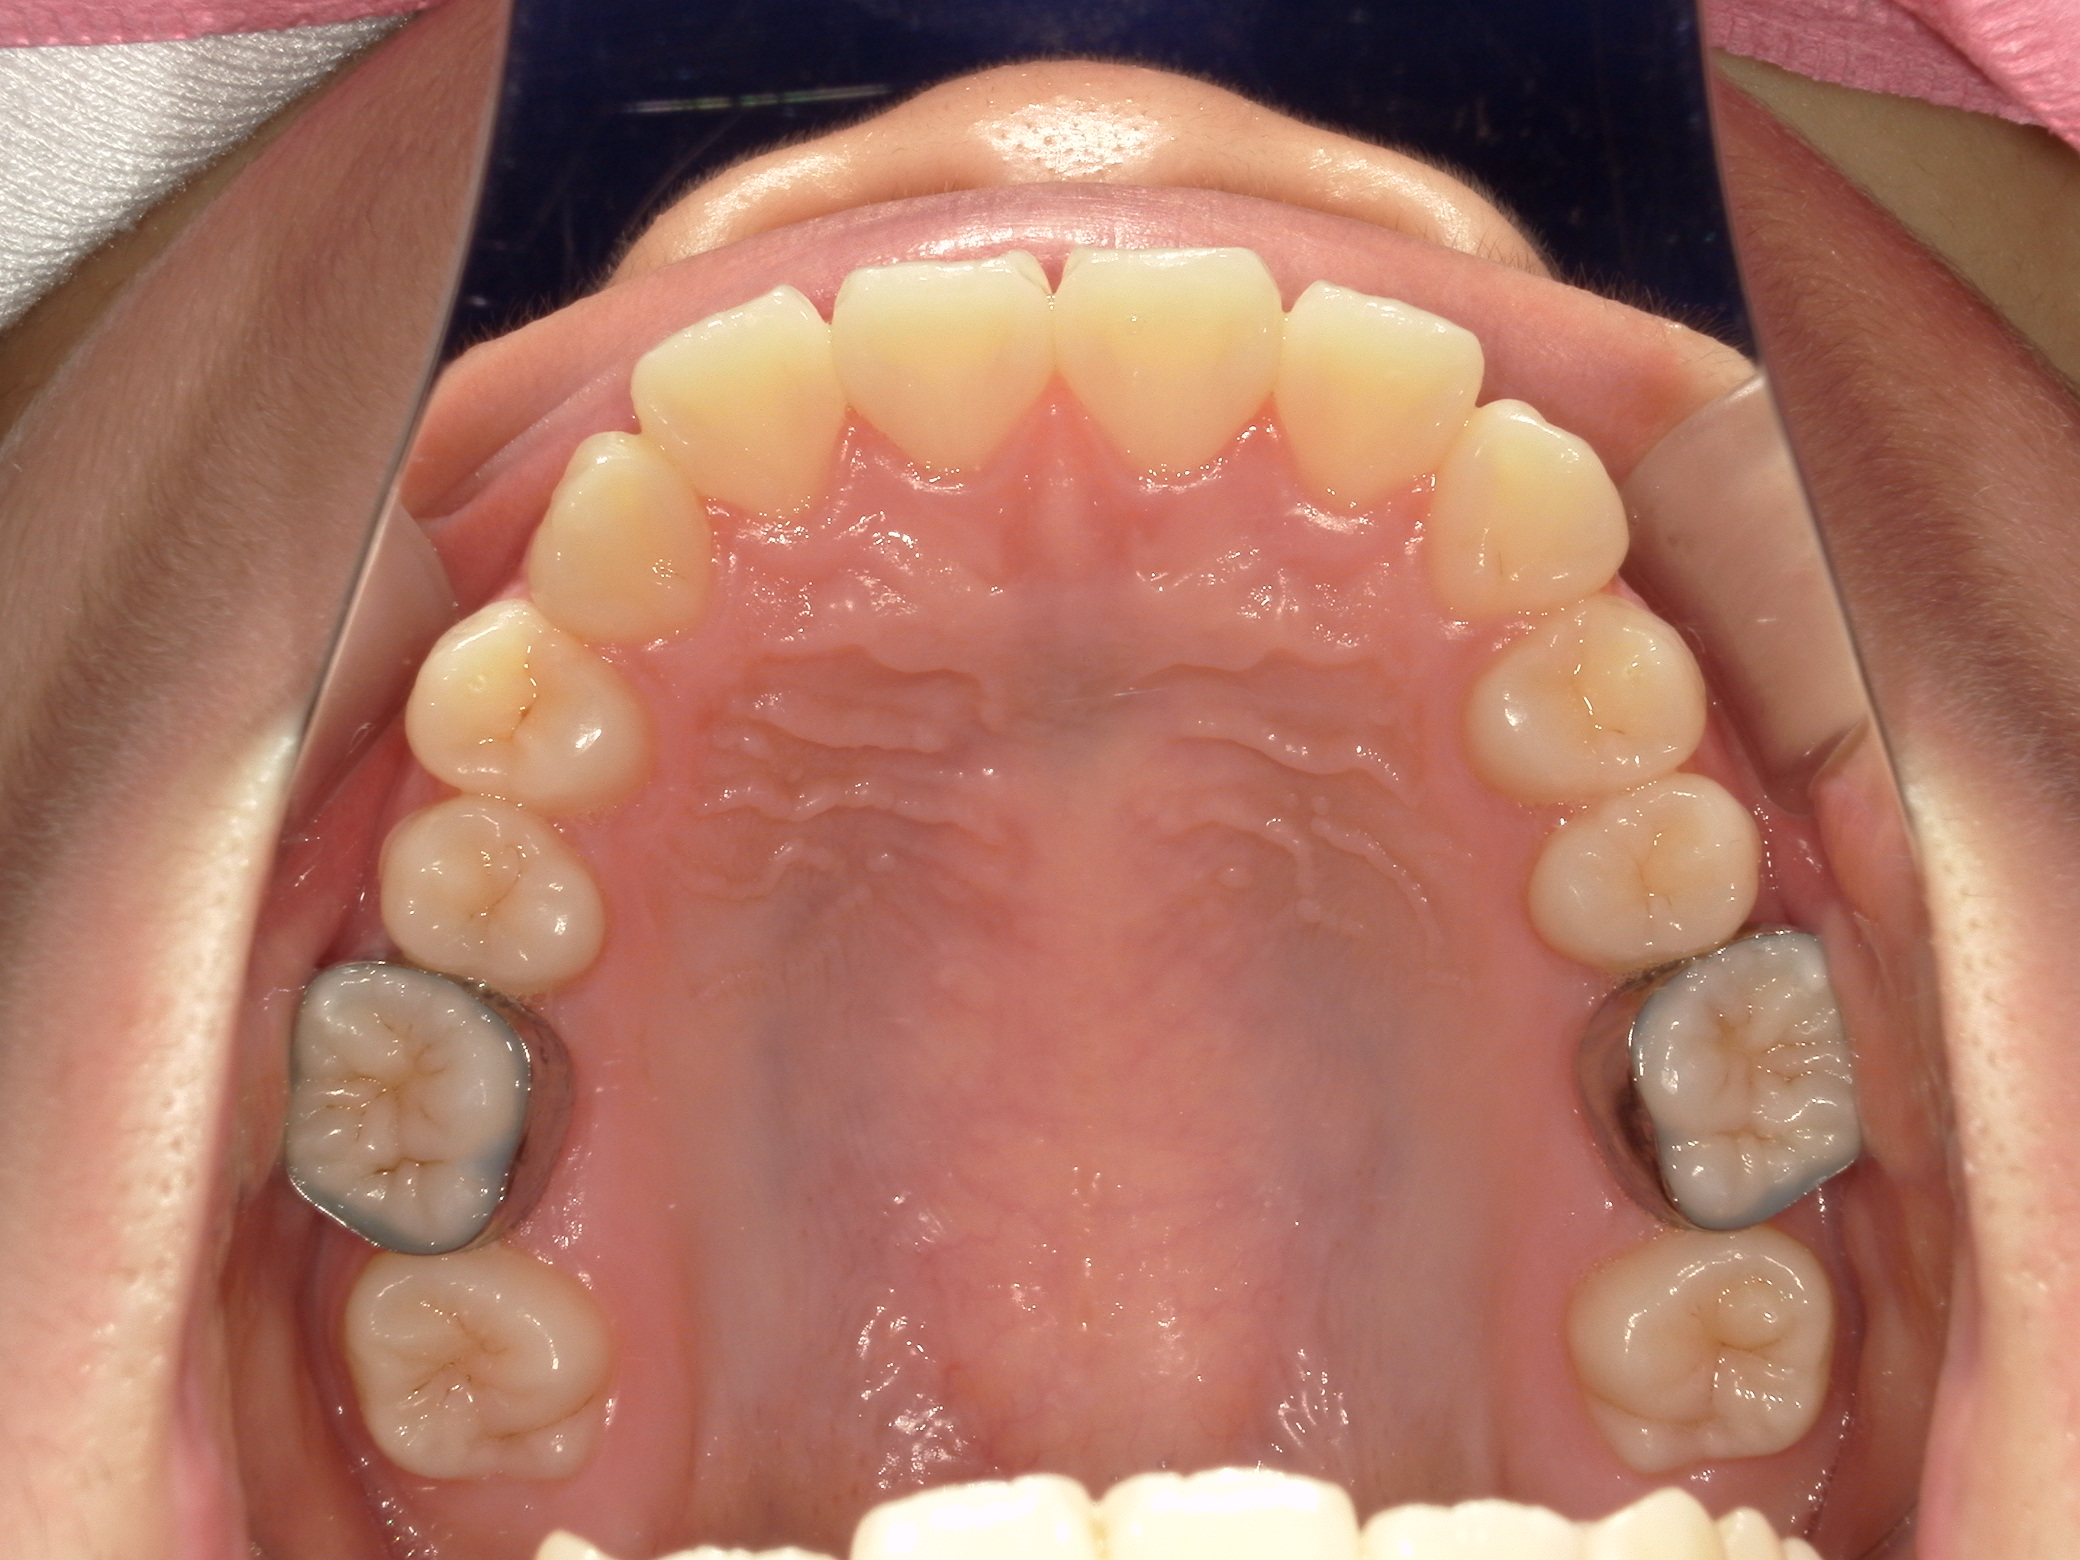

上顎の咬合面は写真の撮り忘れで、模型の咬合面観で代用しています。